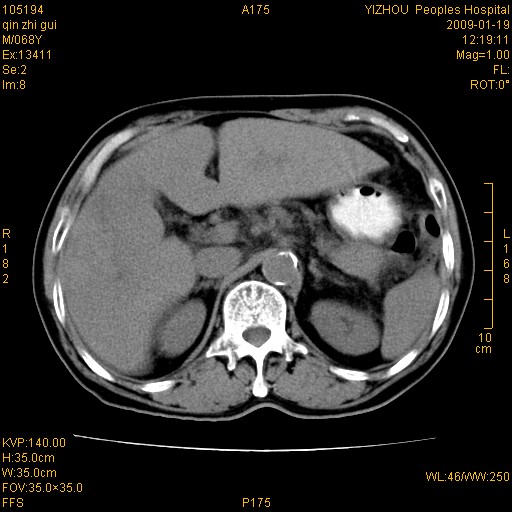

以下是引用随光逐影在2009-1-21 16:11:00的发言:[br]1)考虑肝右叶肝癌并肝静脉及门静脉瘤栓形成。2)肝硬化,少量腹水。3)胆囊炎。4)右侧少量胸腔积液。

病灶外缘凹凸不平,平扫低密度,增强动脉期有强化,门脉早显,静脉期及延期呈延迟强化,结合病史考虑右肝前叶巨块型肝癌可能性大,强化表现不除外胆管细胞癌